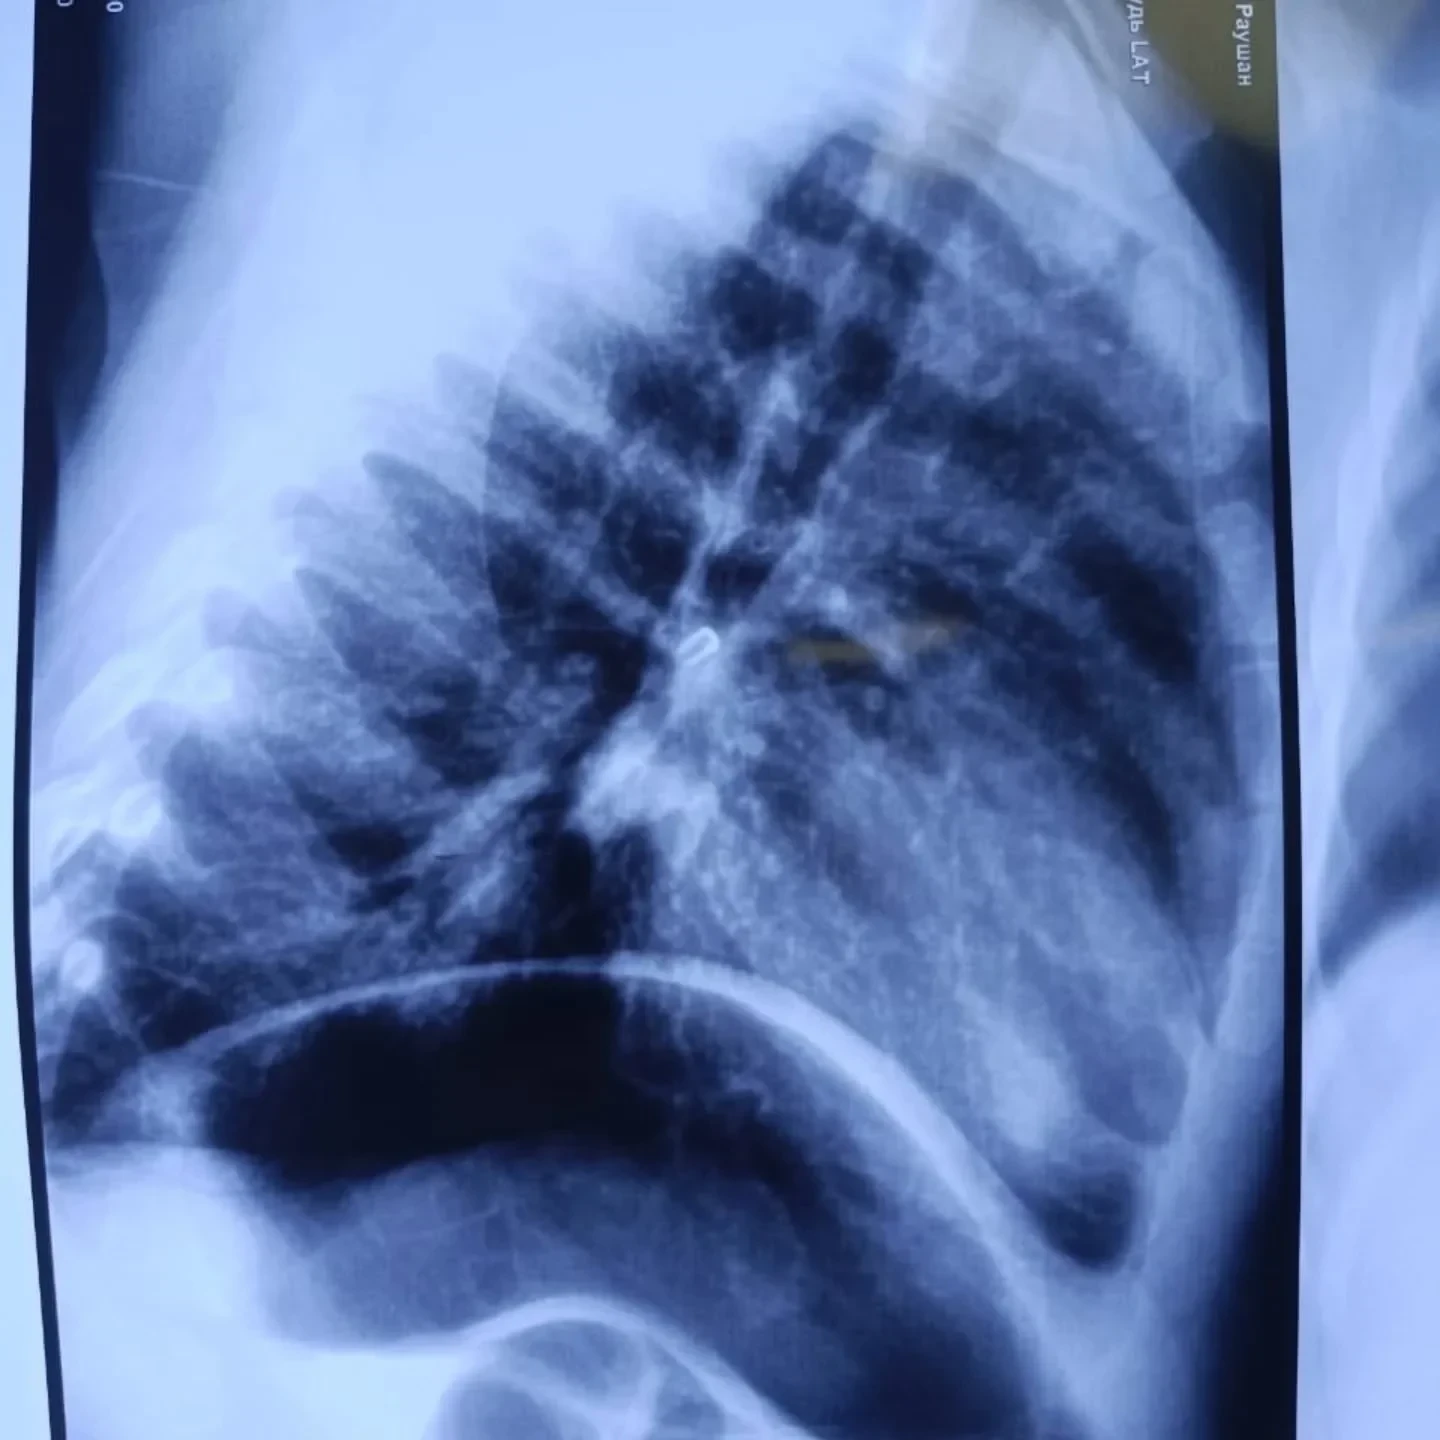

При поступлении в больницу состояние малыша оценивали как тяжелое, так как у него наблюдалась дыхательная недостаточность. Рентгеновское исследование выявило инородное тело в области правого главного бронха.